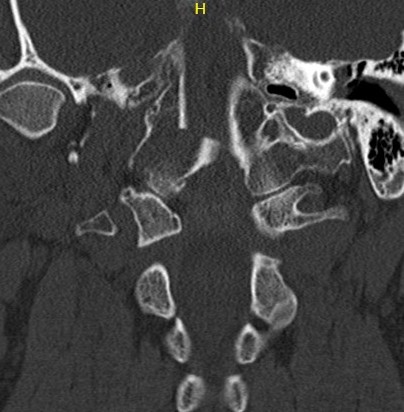

Type II: Occipital condyle fracture involving base of skull

Type III: Inferomedial alar ligament avulsion

Type II: Basal skull involvement